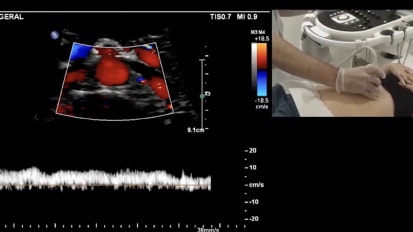

Chapters Transcript Video Left Refluxing Perforating Vein Ablation with Venclose Maven™ Perforator Catheter Featuring: Dr. Jeffrey Carr; Duration: 13 minutes A 46 year old man who has had a very long standing chronic disease of very very strong family history. And he came to me uh complaining of years and years of heaviness, aching, tired, fatigue in his legs, the throbbing and restless legs and cramping. And not to mention, he had over 12 episodes of recurrent thrombophlebitis in both legs. The left leg was worse than the others uh than the right. Um He underwent laser ablation therapy 15 years ago by another provider just of the thigh portion of the great sinus vein, but really did not achieve really any significant improvement over the ensuing years. On his initial duplex ultrasound, we showed closure of that thigh portion of the great sinus vein, but pathologic reflux of bilateral great sap anus and small sinus veins as well as a very large left distal calf perforator of 5.8 centime millimeters and 1942 milliseconds of reflux. Now, he had focal pain over the site of this distal calf perforator that persists despite treatment of his left great sinus vein. And so that's the focus of our intervention today. Uh In addition, because of his recurrent thrombophlebitis is at high risk uh for additional episodes, they've been very painful. Um And he has many superficial vars as well. Uh, that had drained into the superficial system that we will plan on tackling later with phlebectomy. We wanna look at our treatment length that we think we can adopt from that distal end. Yeah, you come, come back, do five. Ok. Just stay right there. That's good. That's good. Ok. So that's do not cross mark that, that's our, that's our safety distance. And now we're gonna move from there to the entrance. We believe that where we think we're gonna angle in on access right about a little more. OK? So just over 22 centimeters or 20 millimeters, this is a five millimeter coil. It's important not to overdo the lidocaine your wheel. Uh These veins are very vasal reactive. So you gotta be very careful, come up very easy and just put a little wheel there and not too much, just enough so that they don't feel the skin neck again. He has a soft, softer skin. The key is to not to move too much with the sonography and just to find it, you can see the tip. Now, I'm not on the edge of the show me the good lumen, the black lumen. There you go more, a little more. So I'm just about to pierce it. I'm gonna poke, poke through a little bit. No looking real. I think I just grabbed some tissue there. How about now? It feels like it. Anybody see. Ok, I am in the vessel. I'm gonna hold really still. I like my assistant to put that in because I'm focusing on not moving an iota and now you say I landed the plane, not at the beginning of the runway, but you know, maybe 1/4 of the way and in Korea just put the wire down and it made it to the edge and it actually made the turn. So it's a looped. It's a little loop. No, it's not loop. It's perfect. It's in the PT. So I'm in the vessel. I'm gonna take my wire out, gonna make a little incision, not my wire, my needle out and then I'm gonna keep that wire right there. We don't wanna lose that position because we, we're pretty pleased that it went in where we hoped I'm gonna make a little skin nick because I don't want resistance when we put the sheath in to pull my wire out. So just a little 11 blade skin nick. And then can you load the space so she'll load this on. I'm just really focusing on not moving that wire and then notice the dilator the distance of the dialer to the sheath. Ok? Because the key is to get the sheet in the dialer is gonna go into that vein, but we're gonna make sure the sheath does. So I'm holding my wire, Casey's gonna show me approaching it. Ok. So we have the dilator in the vein, we have the wire around into the poster tubule. But you can see it's very challenging to know where the sheath begins. And then what's where the sheath and the dilator are in relation on the ultrasound. So that's why it was important to look at how much I'm going to anchor the dilator now. Ok. That's a great view. You can see the double density. I'm gonna just try to advance the sheath in over the dilator here without pushing the dilator and, and that's it. So now my sheet is in and I'm pulling the dilator out and we have that wire in a good position. So I think we can pull everything out, right? We're going to OK. And then we have feedback that we're in the lumen. Wonderful little flesh, please. I'm gonna jiggle just a little. So here I am to the right. I'm not even in it yet. I gotta shallow. My angle of it. Oh, there it is. Right. OK. We're coming into the top into that tributary. Now, you can see the truck, the needle, but I'm off plane. So she's gonna open up the lu in there. I'm not moving right there. I wanna see, I'm gonna aim for her target right there. So I moved laterally and I think right there, I'm in a good position as I enter in. Can you flush that real quick. Just a light little flush. We're going to just flush that again. That's our feedback. It's very challenging. But I think when we flush, we'll be able to see, um, see the tip of the catheter, just light little flush. Ok. That's good. And you see the bubble, so we know where tip is really at the edge of our right where that turn was. So we're in really good position. I'd rather be too far forward than not in the vein. So now we're inserting the maven which has markings on it and the five millimeter tip, I'm anchoring this very firm not to pull back. And I'm really just wanna come in with the maven. You can see it coming in now and I'm gonna go right to that edge and I think that's right where we initially preplanned pretty close. I'm gonna pull back now with the sheath, I'm gonna remove the sheath completely. Very careful not to let the maven come back. It's very lubricious, slippery and it can easily come out if you're not anchoring it. Yeah. So make sure you got dry hands and catheter that we're in good position. I like to note on the skin where we are, you have a number there four on the skin. So it's about, it's just under four and now we're gonna check our distal tip just like we did on the pre and we're gonna try to locate the coil and I could see this many wants to come and point to it, please. So the tip, the plastic tip is right at the junction. Correct, right down there. It's very hard to see it, but it's right there. And 3.5 millimeters from there to, to the coil is the beginning of the coil. So it looks like the coil starts right there. Go ahead and measure that. And that's confirmatory. Yeah. 3.5. We're perfect. So we're very confident that dense white is the beginning is the five millimeter coil. Can you measure the coil itself just to show that we're all on the same page. This is so important to take your time and make sure you know exactly what it is because so I'm gonna put it in there. I'm gonna show I'm pushing it in just to show the coil five millimeter coil. There it is OK. So take that off. So a little pinch here, fill some burn. So you can see my needles perfect. It's going right to the tip and I'm pushing the posterior tibial vein away from my treatment location. Again, I'm gonna pull back before I heat here. I'm a little distal and again, I'm kinda going on all sides of this thing. I'm gonna come back a little bit a lot more just to get this point here. We also want to stay away from the skin is another hazard, five millimeters or greater. Here we go first treatment. So we're getting feedback from the generator. But at the same time, it's important to look at the ultrasound and see if you're getting treatment affect where you think, where you believed it was occurring. So we're exactly where we hoped and thought you could see the e echo density occurring. Often. You'll see a little scintillating or bubbling, boiling of the blood. And this is our second treatment cycle. 22nd cycles. Target is about 100 and 30 °C. You don't feel anything, not a thing. He's enjoying the ride and we're starting to see some echo density, meaning we have treatment effect. We're getting coagulum, we're denuding the endothelium of the vein to destroy it on and create inflammation. So I'm very pleased with this location at the deep and we're well enough away from the posterior tibial vein there. From experience to date. We have, we've been able to inform ourselves about this. We early on in the original study. Um the ID E trial, we worked from one treatment per location to six. We found safety at either one of those uh strategies, but we saw a few pas early on when it was just a one and done uh location. Um I think there are a lot of variables that go into it. Um I believe if you're in the lumen and are absolutely certain, you know, you're gonna deliver the therapy. But uh we've been practicing and recommending up front the six So I'm gonna stop here. We did six. We're gonna recommend six per location up front to get clo the best chance for closure. So I'm gonna be staring down here to pull back five and my and Casey's gonna be looking to see if it matches up what we think on the screen. So here I go, I'm pulling back and that's in the middle of the next one. So we think that's five. You agree? Yeah, there could be, there could, there could be plaques. I'm sorry, there could be slack stored in the catheter. You may not be pulling back. Exactly five. So just kind of be aware of that. You see the poster tibial head flow and you see that's the closed perforator there, you can see it to the top left here where it drained in and we see complete closure uh from the, from the treatments today. And then now I just show the posterior tibial really try to line that out and we have flow. There you go. Now we're really laying it out and it's hard when there's compressed images. So uh do your best. Uh the best is to follow up with these patients. Published December 13, 2024 Created by Related Presenters Jeffrey Carr, MD, FACC, FSCAI Interventional Cardiology, Cardiovascular Disease, Internal MedicineCHRISTUS Trinity Clinic View full profile